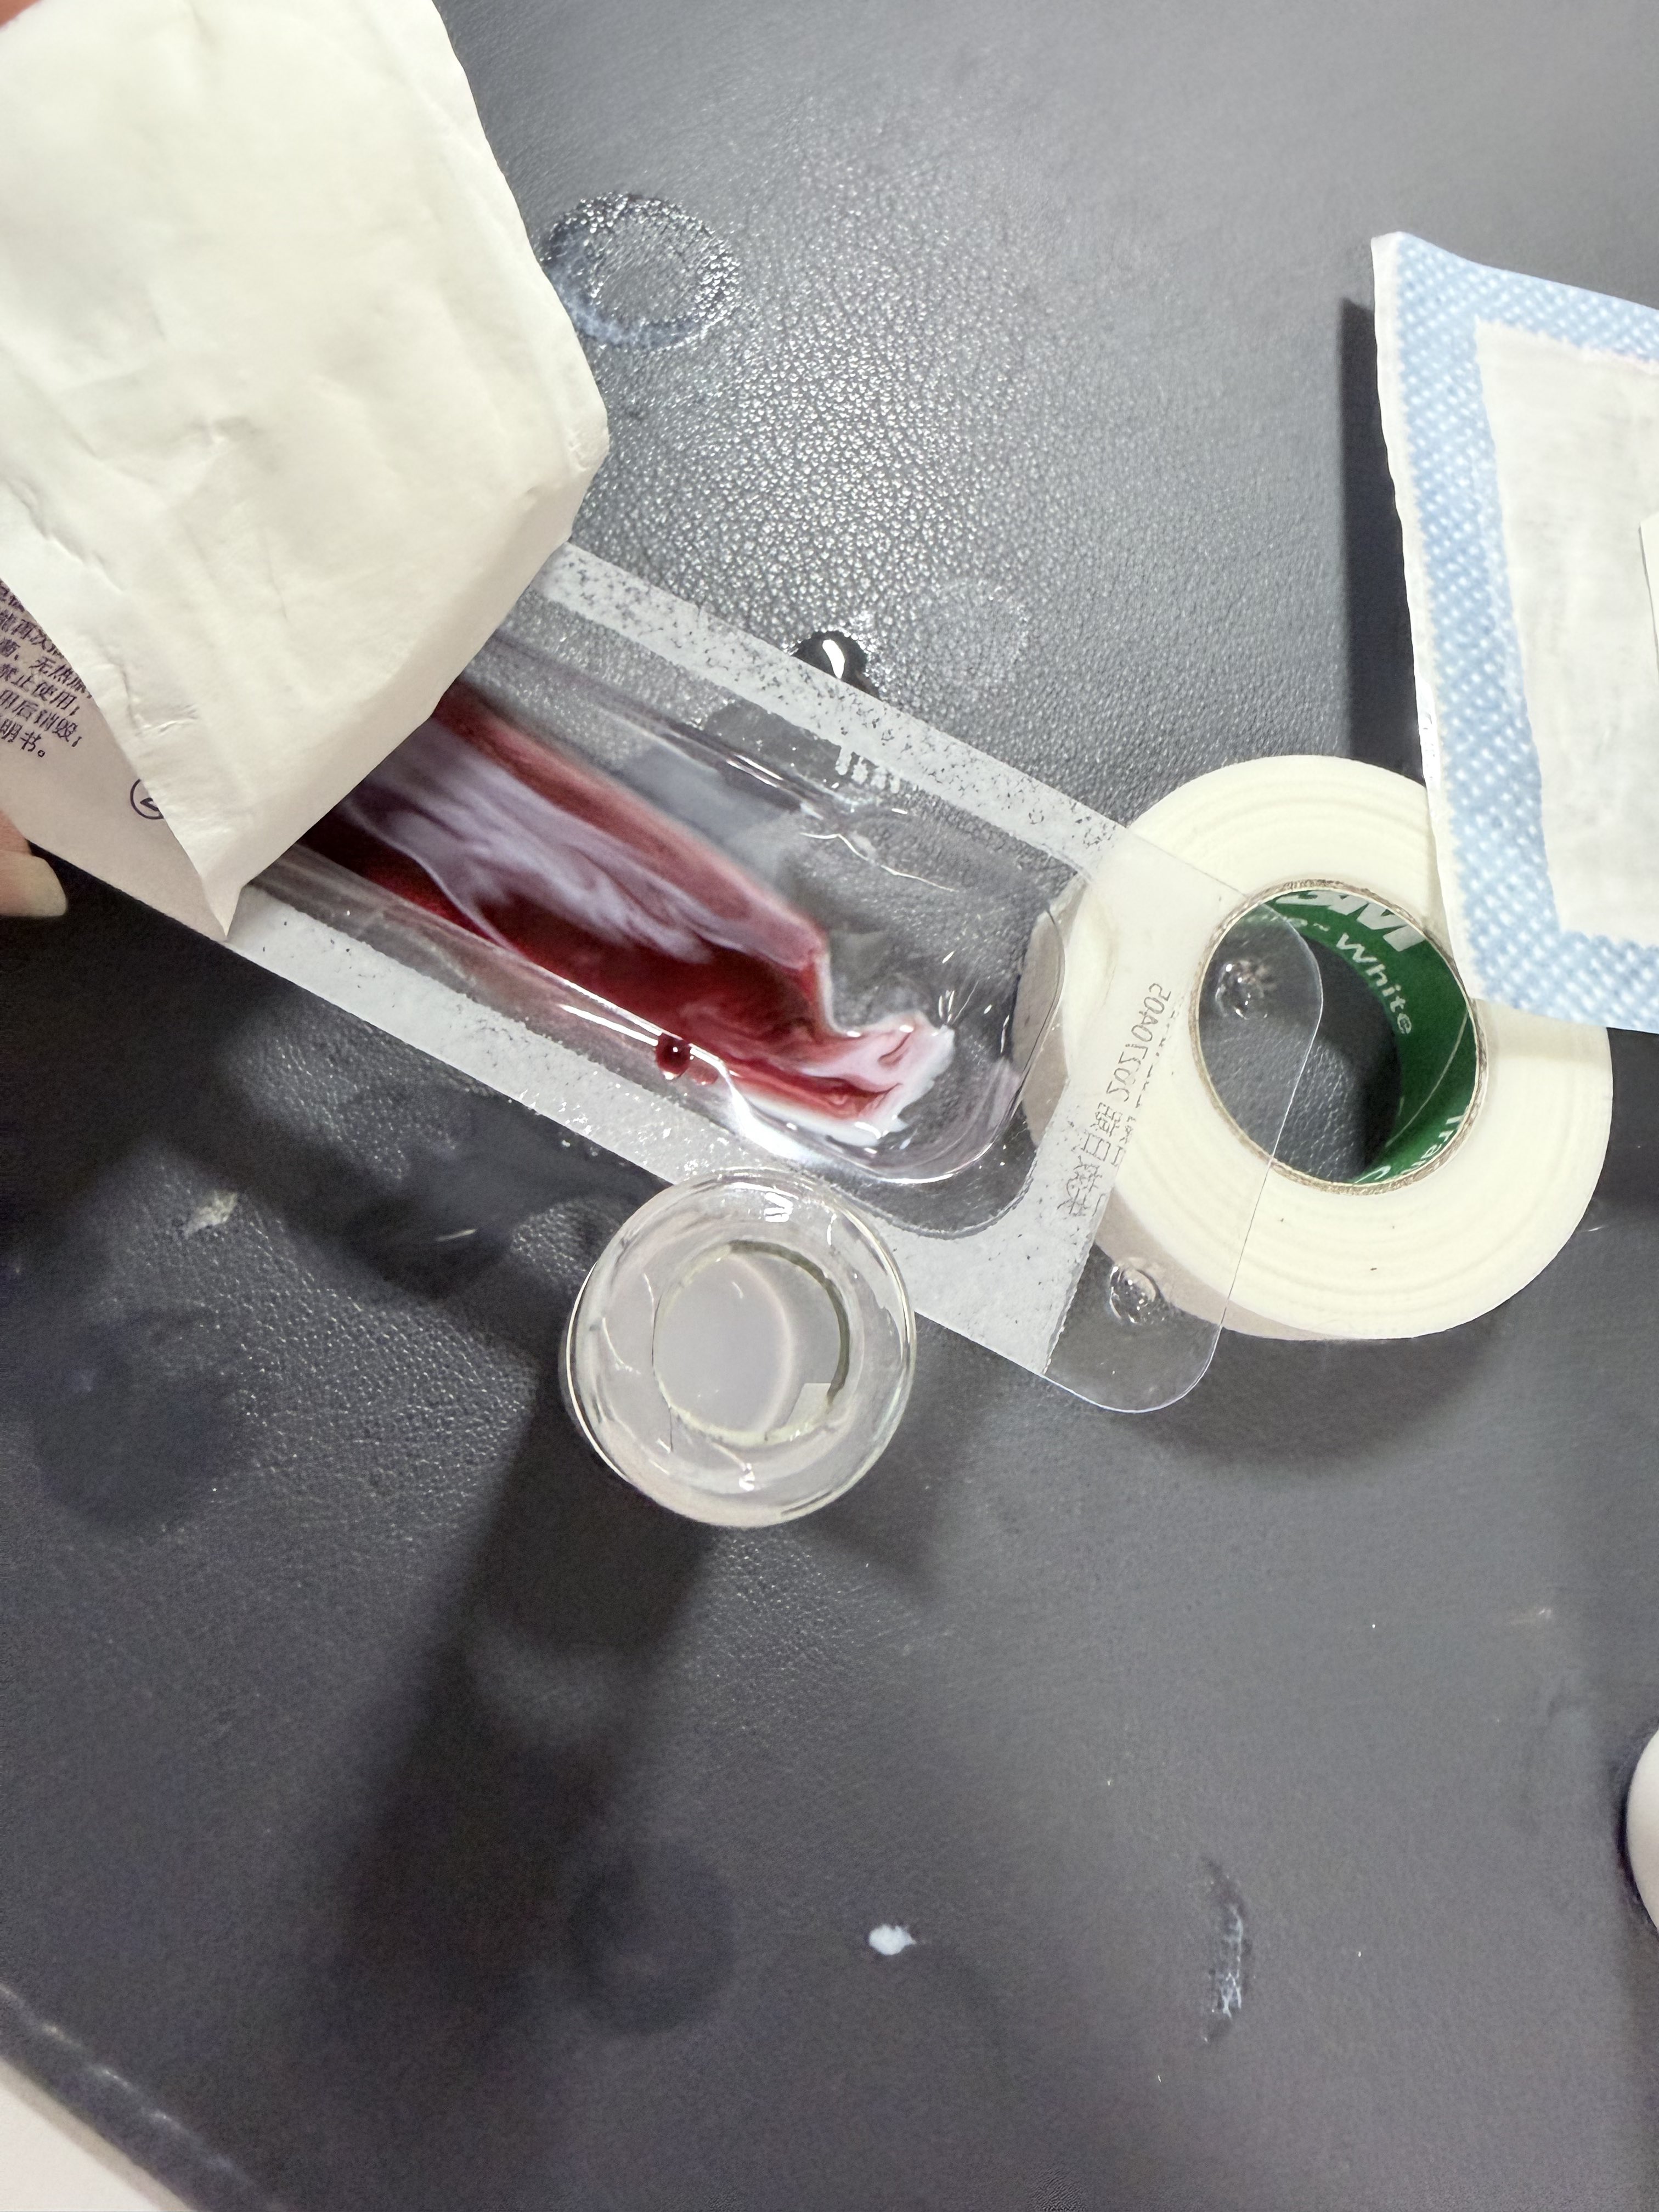

关于疤痕管理..?

因为皮肤比较容易过敏用不了疤痕贴这类的所以一般都用软膏或凝胶()

左边的只能用于已经愈合的创伤!右边的可以用于创面,还有人表皮因子生长凝胶或许也可以,都有不止祛疤的功能⬇️

曾经有一段时间一直在坚持用乳膏,在我这里的功能更像是一种仪式…有时候甚至可以对抗自伤冲动 https://t.co/PFB5AIisHE